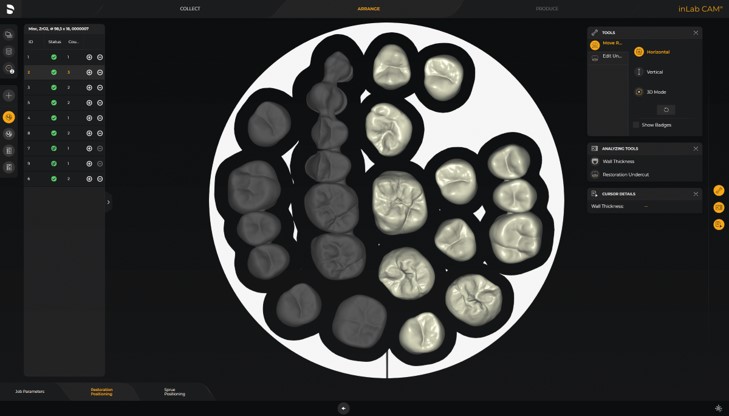

デンツプライ シロナ ミリングバー thumb_4571204905164_1.jpgの詳細情報

thumb_4571204905164_1.jpg。プロテーパーネクスト [デンツプライシロナ] 25mm X2の通販 | Ci。inLab MC X5:歯科用ミリングマシン | デンツプライシロナ 日本。箱の中に入ってますミリングバーは未使用品となります。。3本のみです。ハート型ギベオン 2粒。使用する事が無くなりましたので、出品させていただきました。⊰ 煌蘭 ⊱ 専用。画像をご確認の上、ご購入宜しくお願いいたします。コットンピコット(よごれあります)(残2かせ)。